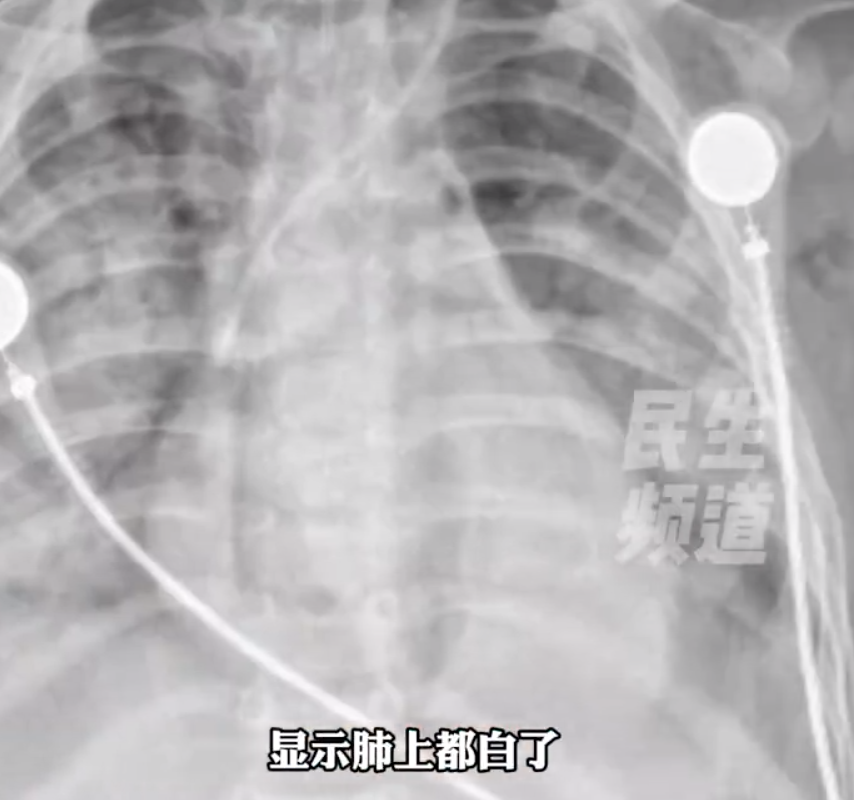

1岁男童误喝紫草油

催吐不当进ICU

近日,河南南阳的一个1岁宝宝,因误喝10ml婴儿紫草油,吸入肺中被送进ICU抢救。据妈妈回忆,她发现宝宝误喝婴儿紫草油时,大声制止,并紧急抠嗓子催吐。“油脂吸入了肺里,形成了肺部油脂性感染。宝宝受惊呛到了,他才1岁刚学会走路,都是我的操作失误。”